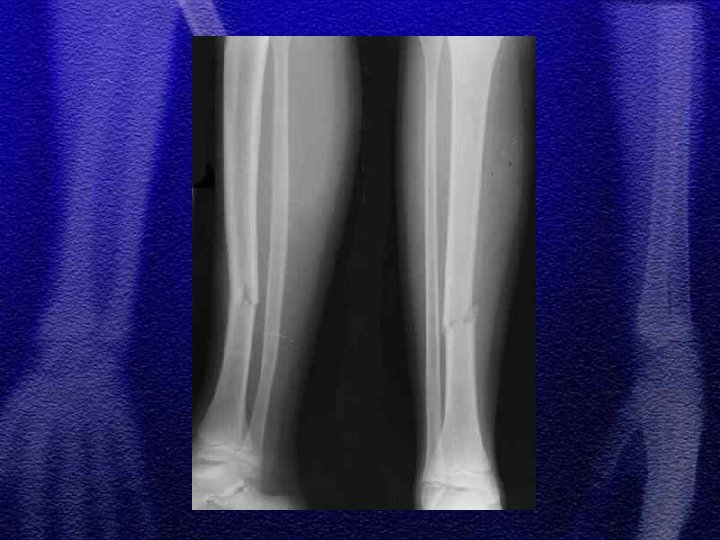

§ Leczenie zachowawcze jest zasadniczym postępowaniem, niezależnie od wieku dziecka § Dopuszczalne skrócenie odłamów do 1 cm § Dopuszczalne załamanie osi do 10° § Dopuszczalne przemieszczenie do boku o 2/3 szerokości trzonu

§ Przy wtórnych przemieszczeniach kątowych stosuje się gipsotomię § Leczenie operacyjne: złamania otwarte, złamania niestabilne - ZESPOL, śruby, stabilizatory zewnętrzne